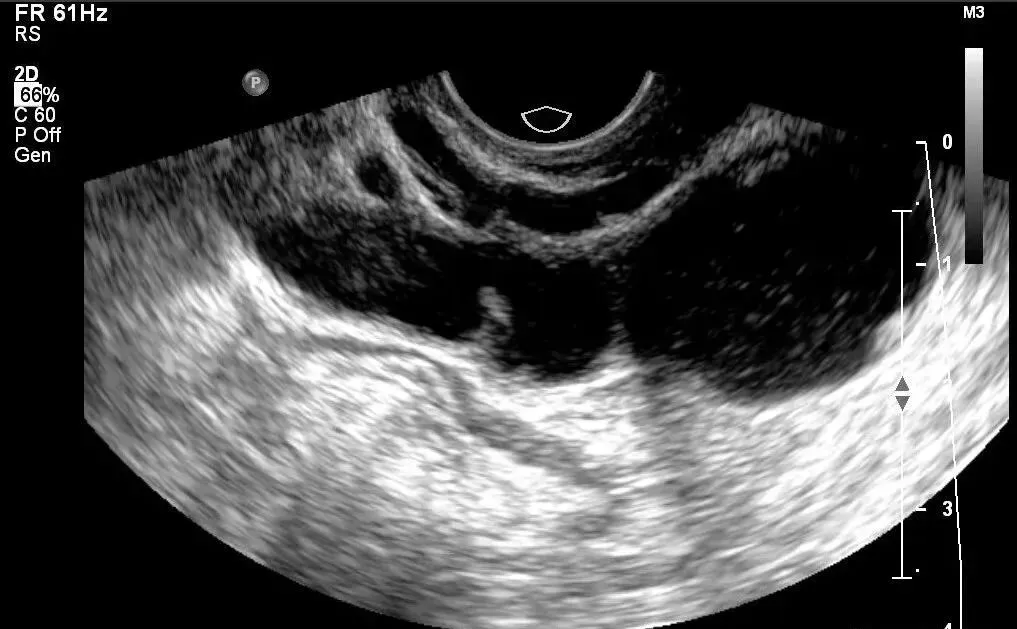

子宫腺肌症

●子宫腺肌病好发于已生育、多产或有多次宫腔操作史的妇女,少数也可发生在年轻、无婚育及宫腔操作史的女性,它是由于具有功能的子宫内膜腺体细胞及间质细胞向肌层内侵蚀而产生的病变,伴随着子宫平滑肌细胞的增生。

●分类:弥漫型子宫腺肌病(最常见):子宫体弥漫性对称或不对称性增大,呈球形。

局灶性子宫腺肌病,边界不清,未见明显包膜,内部血供增多。

子宫增大,子宫后壁比前壁肌层厚,后壁肌层呈栅栏样改变(箭头示)